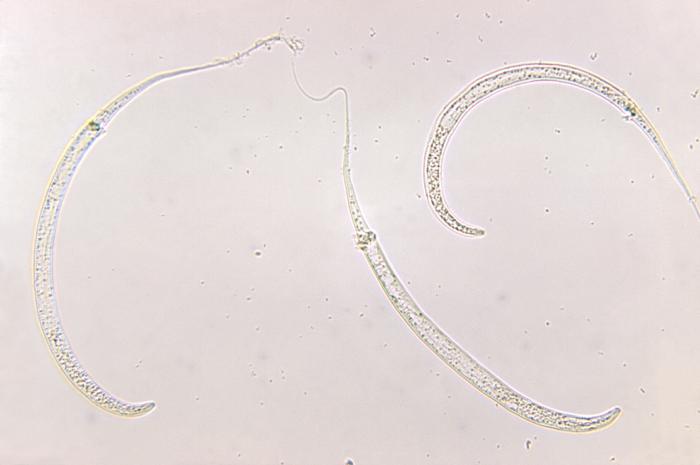

Dracunculiasis, also called Guinea Worm illness, is attributable to the parasitic roundworm – Dracunculus medinensis. The which means of Dracunculiasis in Latin is ‘ with little dragons.’